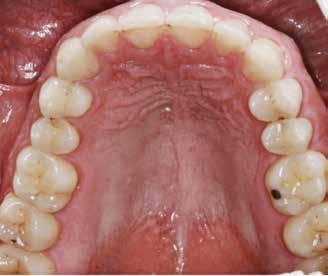

Okklusalt billede af A) over- og B) underkæbe

2. Klinisk ses tydelig slitage ind i dentinen på samtlige tænder fra 6’er til 6’er i begge kæber.

Fig. 2. Clinically, extensive wear into the dentin of all teeth in both jaws is observed.